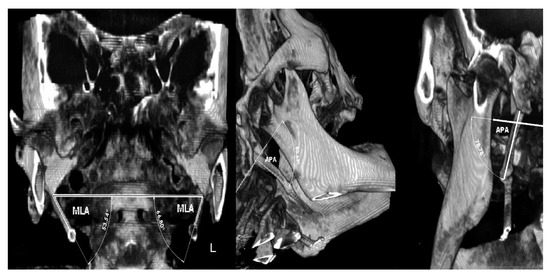

Due to suspicion that this patient belongs to the Eagle’s syndrome group, additional angle measurements were performed. The measurements of important angles for 3D visualization of the SHC showed: right 53.54° (short) and left 66.8° (~normal) for the mediolateral angle (MLA), right 80.63° and left 78.78° (elongated) for the anteroposterior angle (APA), indicating wide both angles [9]. Measurements of maximum thickness with values of 4.56 mm and 3.6 mm (normal) for the right and left sides were seen, respectively. On both sides, the pattern of calcification/mineralization was almost identical, involving the tympanohyal, stylohyal, ceratohyal and hypohyal parts of the SHC (Figure 6).

Figure 6. 3D measurement of angles for analyzing a “normal-pathological” SHC: (left) measurements of mediolateral angling (MLA) of a calcified/ossified coronal 3D-CBCT image; (middle) measurements of right anteroposterior angling (APA) of a calcified/ossified SHC with the longitudinal axis of the SHC and Mc Rae’s line; (right) measurements of left anteroposterior angling (APA) of a calcified/ossified SHC with the longitudinal axis of the SHC and Mc Rae’s line.